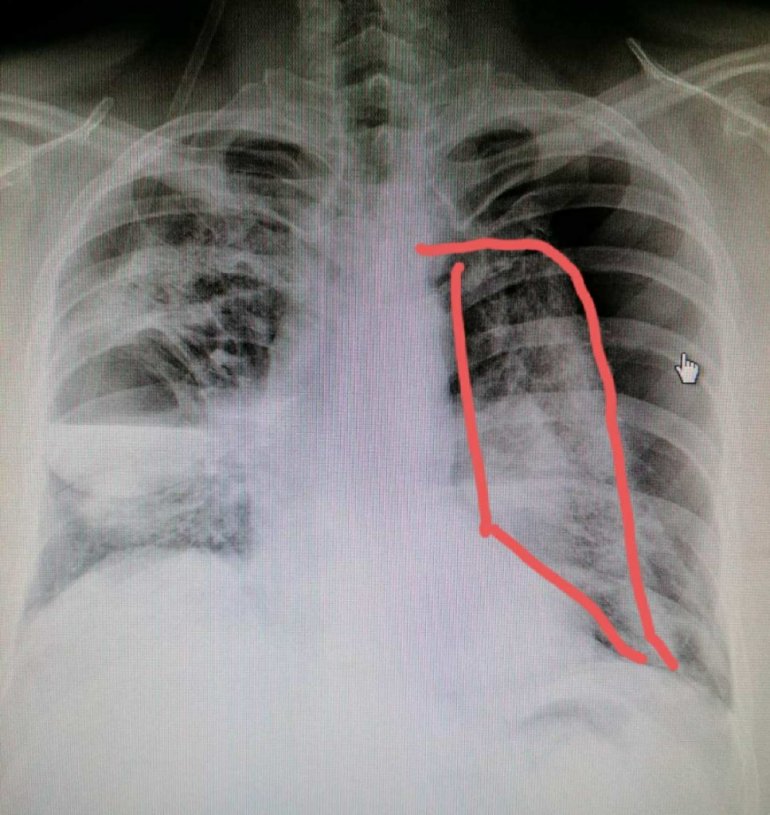

– Nadam se da mi nećete zameriti. Snimci su uznemirujući. Treći je normalan snimak pluća. Prva dva – obostrani Pneumotoraks, pucanje plućne maramice, gnojne šupljine u plućima, sepsa, posledica Kovid19. Muškarac, 40 godina. Već tri meseca se leči u tercijarnoj ustanovi. Sada je stabilan – bila je njena objava na Tviteru uz priložene fotografije rendgenskog snimka pluća.

– Dolazi do pucanja plućna maramice i sa leve strane, tako da se razvija obostrani pneumotoraks. To je ozbiljno stanje koje životno ugrožava pacijenta. Na sve to stvorile su se i gnojne šupljine u plućima, a zatim se razvila i sepsa. Ovakvo stanje, zahteva hitnu intervenciju grudnog hirurga, što je u epidomiološkoj situaciji teško izvodljivo – kaže dr Plavšić.

– Zato mi je ova komplikovana radiološka slika bila jako neobična i zato sam savetovala da se pacijent hitno uputi u referentnu tercijalnu ustanovu, koja se bavi ovom problematikom – kaže nam dr Plavšić.